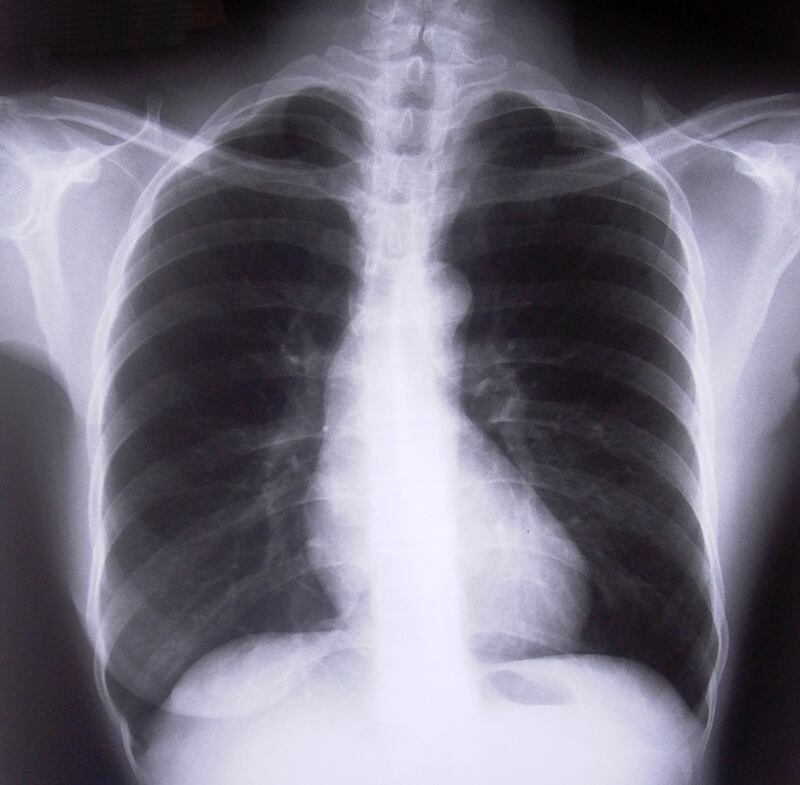

En lugar de mandar señales a las células de los nervios que permiten que la persona huela, estas partes del pulmón detectan el olor y envían señales a las neuronas para que envíen hormonas que contraigan las vías respiratorias.

O sea, detectan si hay algún olor que pueda representar una amenaza y hacen que no se inhale. Por esta razón, la persona muchas veces tose y le cuesta respirar ante el humo o sustancias con olor penetrante.

El estudio, publicado en la revista American Journal of Respiratory Cell and Molecular Biology , describe estas estructuras como un nuevo tipo de célula llamado células pulmonares neuroendocrinas (PNECs, por sus siglas en inglés).

Si algún químico se detecta como nocivo, estos receptores mandan impulsos al cerebro que hacen que las vías respiratorias se contraigan para evitar contaminación en los bronquios y pulmones.